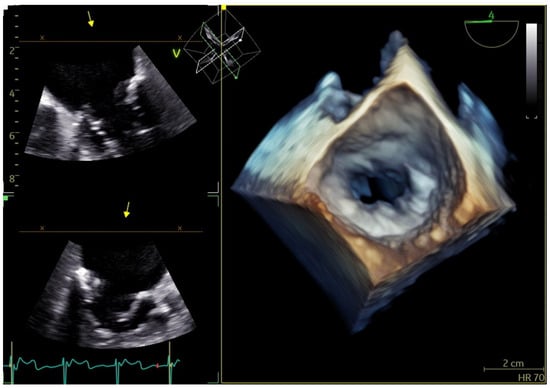

Figure 4.

Three-dimensional TEE: severe MAC involves >270° of the annulus and results in MS due to displacement of the annulus inward. (TEE: transesophageal echocardiography, MAC: mitral annular calcification, MS: mitral stenosis).